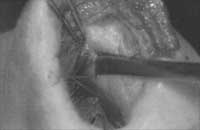

Figure 3. A: Spreader grafts are placed into a pocket between upper lateral cartilage and dorsal septum. A typical graft extends from the osseocartilaginous junction to the anterior septal angle. B: A spreader graft has been carved and is positioned between the dorsal septum and upper lateral cartilage.

Figure 4. A: Bilateral spreader grafts in submucoperichondrial pocket between upper lateral cartilage and septum.